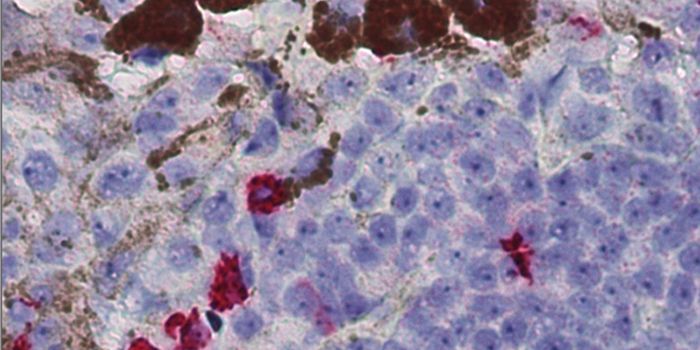

NOV 05, 2015CancerA 41-year old man based out of Columbia has reportedly died of a strange type of cancer that doctors had a lot of troubl ...